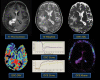

Advanced molecular and pathophysiologic characterization of primary central nervous system lymphoma (PCNSL) has revealed insights into promising targeted therapeutic approaches. Medical imaging plays a fundamental role in PCNSL diagnosis, staging, and response assessment. Institutional imaging variation and inconsistent clinical trial reporting diminishes the reliability and reproducibility of clinical response assessment. In this context, we aimed to: (1) critically review the use of advanced positron emission tomography (PET) and magnetic resonance imaging (MRI) in the setting of PCNSL; (2) provide results from an international survey of clinical sites describing the current practices for routine and advanced imaging, and (3) provide biologically based recommendations from the International PCNSL Collaborative Group (IPCG) on adaptation of standardized imaging practices. The IPCG provides PET and MRI consensus recommendations built upon previous recommendations for standardized brain tumor imaging protocols (BTIP) in primary and metastatic disease. A biologically integrated approach is provided to addresses the unique challenges associated with the imaging assessment of PCNSL. Detailed imaging parameters facilitate the adoption of these recommendations by researchers and clinicians. To enhance clinical feasibility, we have developed both "ideal" and "minimum standard" protocols at 3T and 1.5T MR systems that will facilitate widespread adoption.